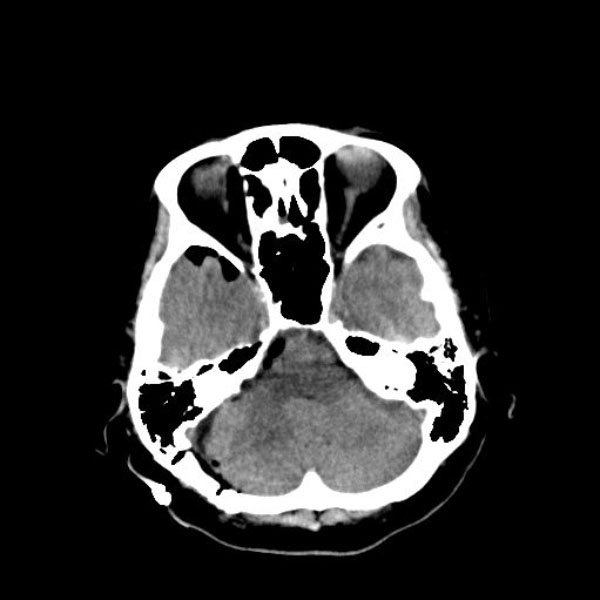

手術前

(MR1)

(CT)